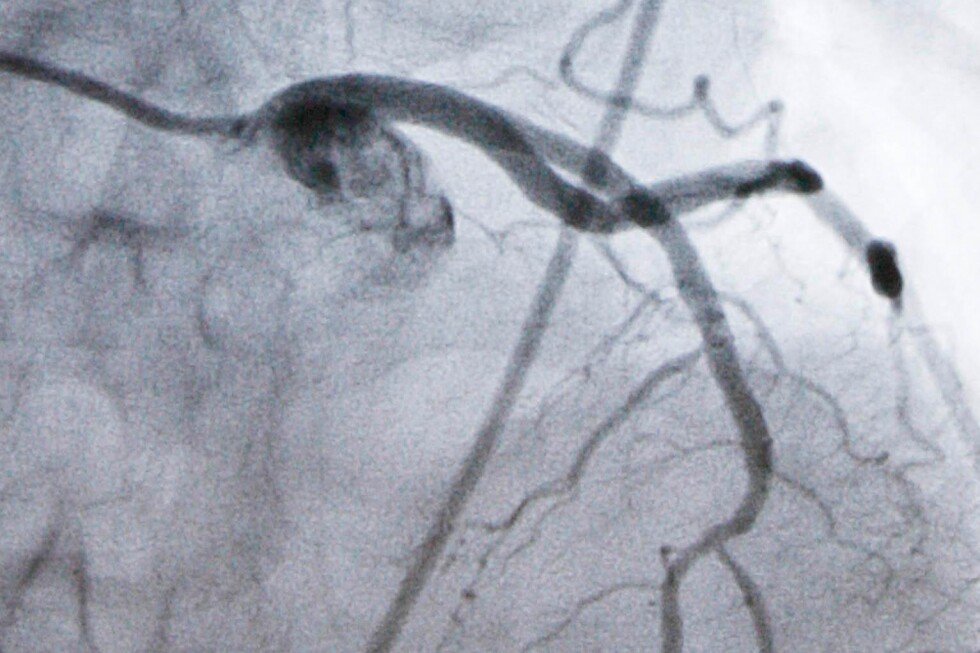

A monitor shows an artery during a catheterization lab heart procedure in Burlington, Vt., Tuesday, Sept. 23, 2008. (AP Photo/Toby Talbot, File) Add AP News as your preferred source to see more of our stories on Google. Share (function () { const counter = document.getElementById("scrollToComments"); const HEADER_OFFSET = 120; function findCommentsModule() { return document.querySelector('.vf3-comments, vf-conversations, '); } function maybeShowCounter() { if (findCommentsModule()) { counter.style.display = "inline-flex"; } else { counter.style.display = "none"; } } // Show only when Viafoura is present maybeShowCounter(); // Watch DOM for late loads const observer = new MutationObserver(maybeShowCounter); observer.observe(document.documentElement, { childList: true, subtree: true }); // Scroll action counter.addEventListener("click", function () { const el = findCommentsModule(); if (!el) return; const top = el.getBoundingClientRect().top + window.scrollY - HEADER_OFFSET; window.scrollTo({ top, behavior: "smooth" }); }); })(); .thin-line-button { display: inline-flex; align-items: center; justify-content: center; border: 1px solid #ccc; height: 30px; padding: 0 10px; cursor: pointer; border-radius: 5px; background: none; text-align: center; font-size: 1.4rem; font-weight: 700; white-space: nowrap; flex-shrink: 0; color: inherit; transition: none; /* Remove animation effect */ } .thin-line-button { color: #000; background: white; } /* Remove hover effect */ .thin-line-button:hover { border: 1px solid #ccc; } .comment-icon { width: 20px; height: 20px; min-width: 20px; min-height: 20px; flex: 0 0 20px; object-fit: contain; display: inline-block; } .Page-actions-commentCounter .embed-caption { display: none; } .vf-comments-count.vf-is-logged-in { margin-left: 4px; } WASHINGTON (AP) — A new kind of pill sharply reduced artery-clogging cholesterol in people who remain at high risk of heart attacks despite taking statins, researchers reported Wednesday. It’s still experimental but the pill helps rid the body of cholesterol in a way that today can be done only with injected medicines. If approved by the Food and Drug Administration, the pill, named enlicitide, could offer an easier-to-use option for millions of people. Statins block some of the liver’s production of cholesterol and are the cornerstone of treatment. But even taking the highest doses, many people need additional help lowering their LDL, or “bad,” cholesterol enough to meet medical guidelines. In a major study, more than 2,900 high-risk patients